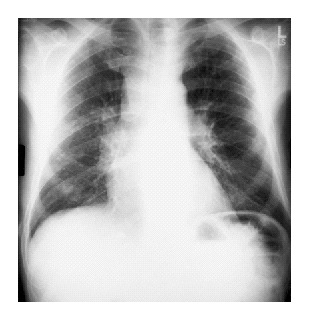

A chest x-ray (Panel A), CT scan of the chest (Panel B) and abdomen (Panel C),

and the results of a barium-enema examination of the small bowel (Panel D) are shown

below.

Panel A.